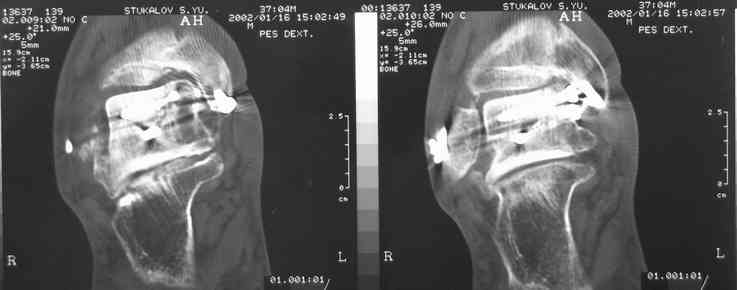

Случай с множественным оскольчатым переломом тарана оперированный из двойного доступа.

Через 2 мес.:

Через 8 мес.:

Через 14 мес.:

И второй случай из недавней ташкентской практики, (извините за качество ренгенограммы и только в одной проекции) случай падения с высоты (кстати моего друга - известного киноактера) - открытый

смещенный перелом тарана, с переломом переднего края дистального эпиметафиза большеберцовой кости.

При поступлении в приемной сделана первичная обработка с ушиванием открытой латеральной раны и вытяжением за пятку.

Из-за отсутствия времени пришлось оперировать на второе утро, из материала, что имеем на месте, фиксирован двумя шурупами, а третий-это контур сломанного жойстика в 4 мм. На дистальный медиальный конец тибиа antiglide 3.5 мм пластина. Через пару дней выписан и несмотря на предупреждение, самостоятельно начал нагрузку в 4 недели, время не ждет, снимается в боевике в Росийской Федерации.

(кстати, на нашем случае была применена костная пластика-allograft crouton для заполнения дефектов)